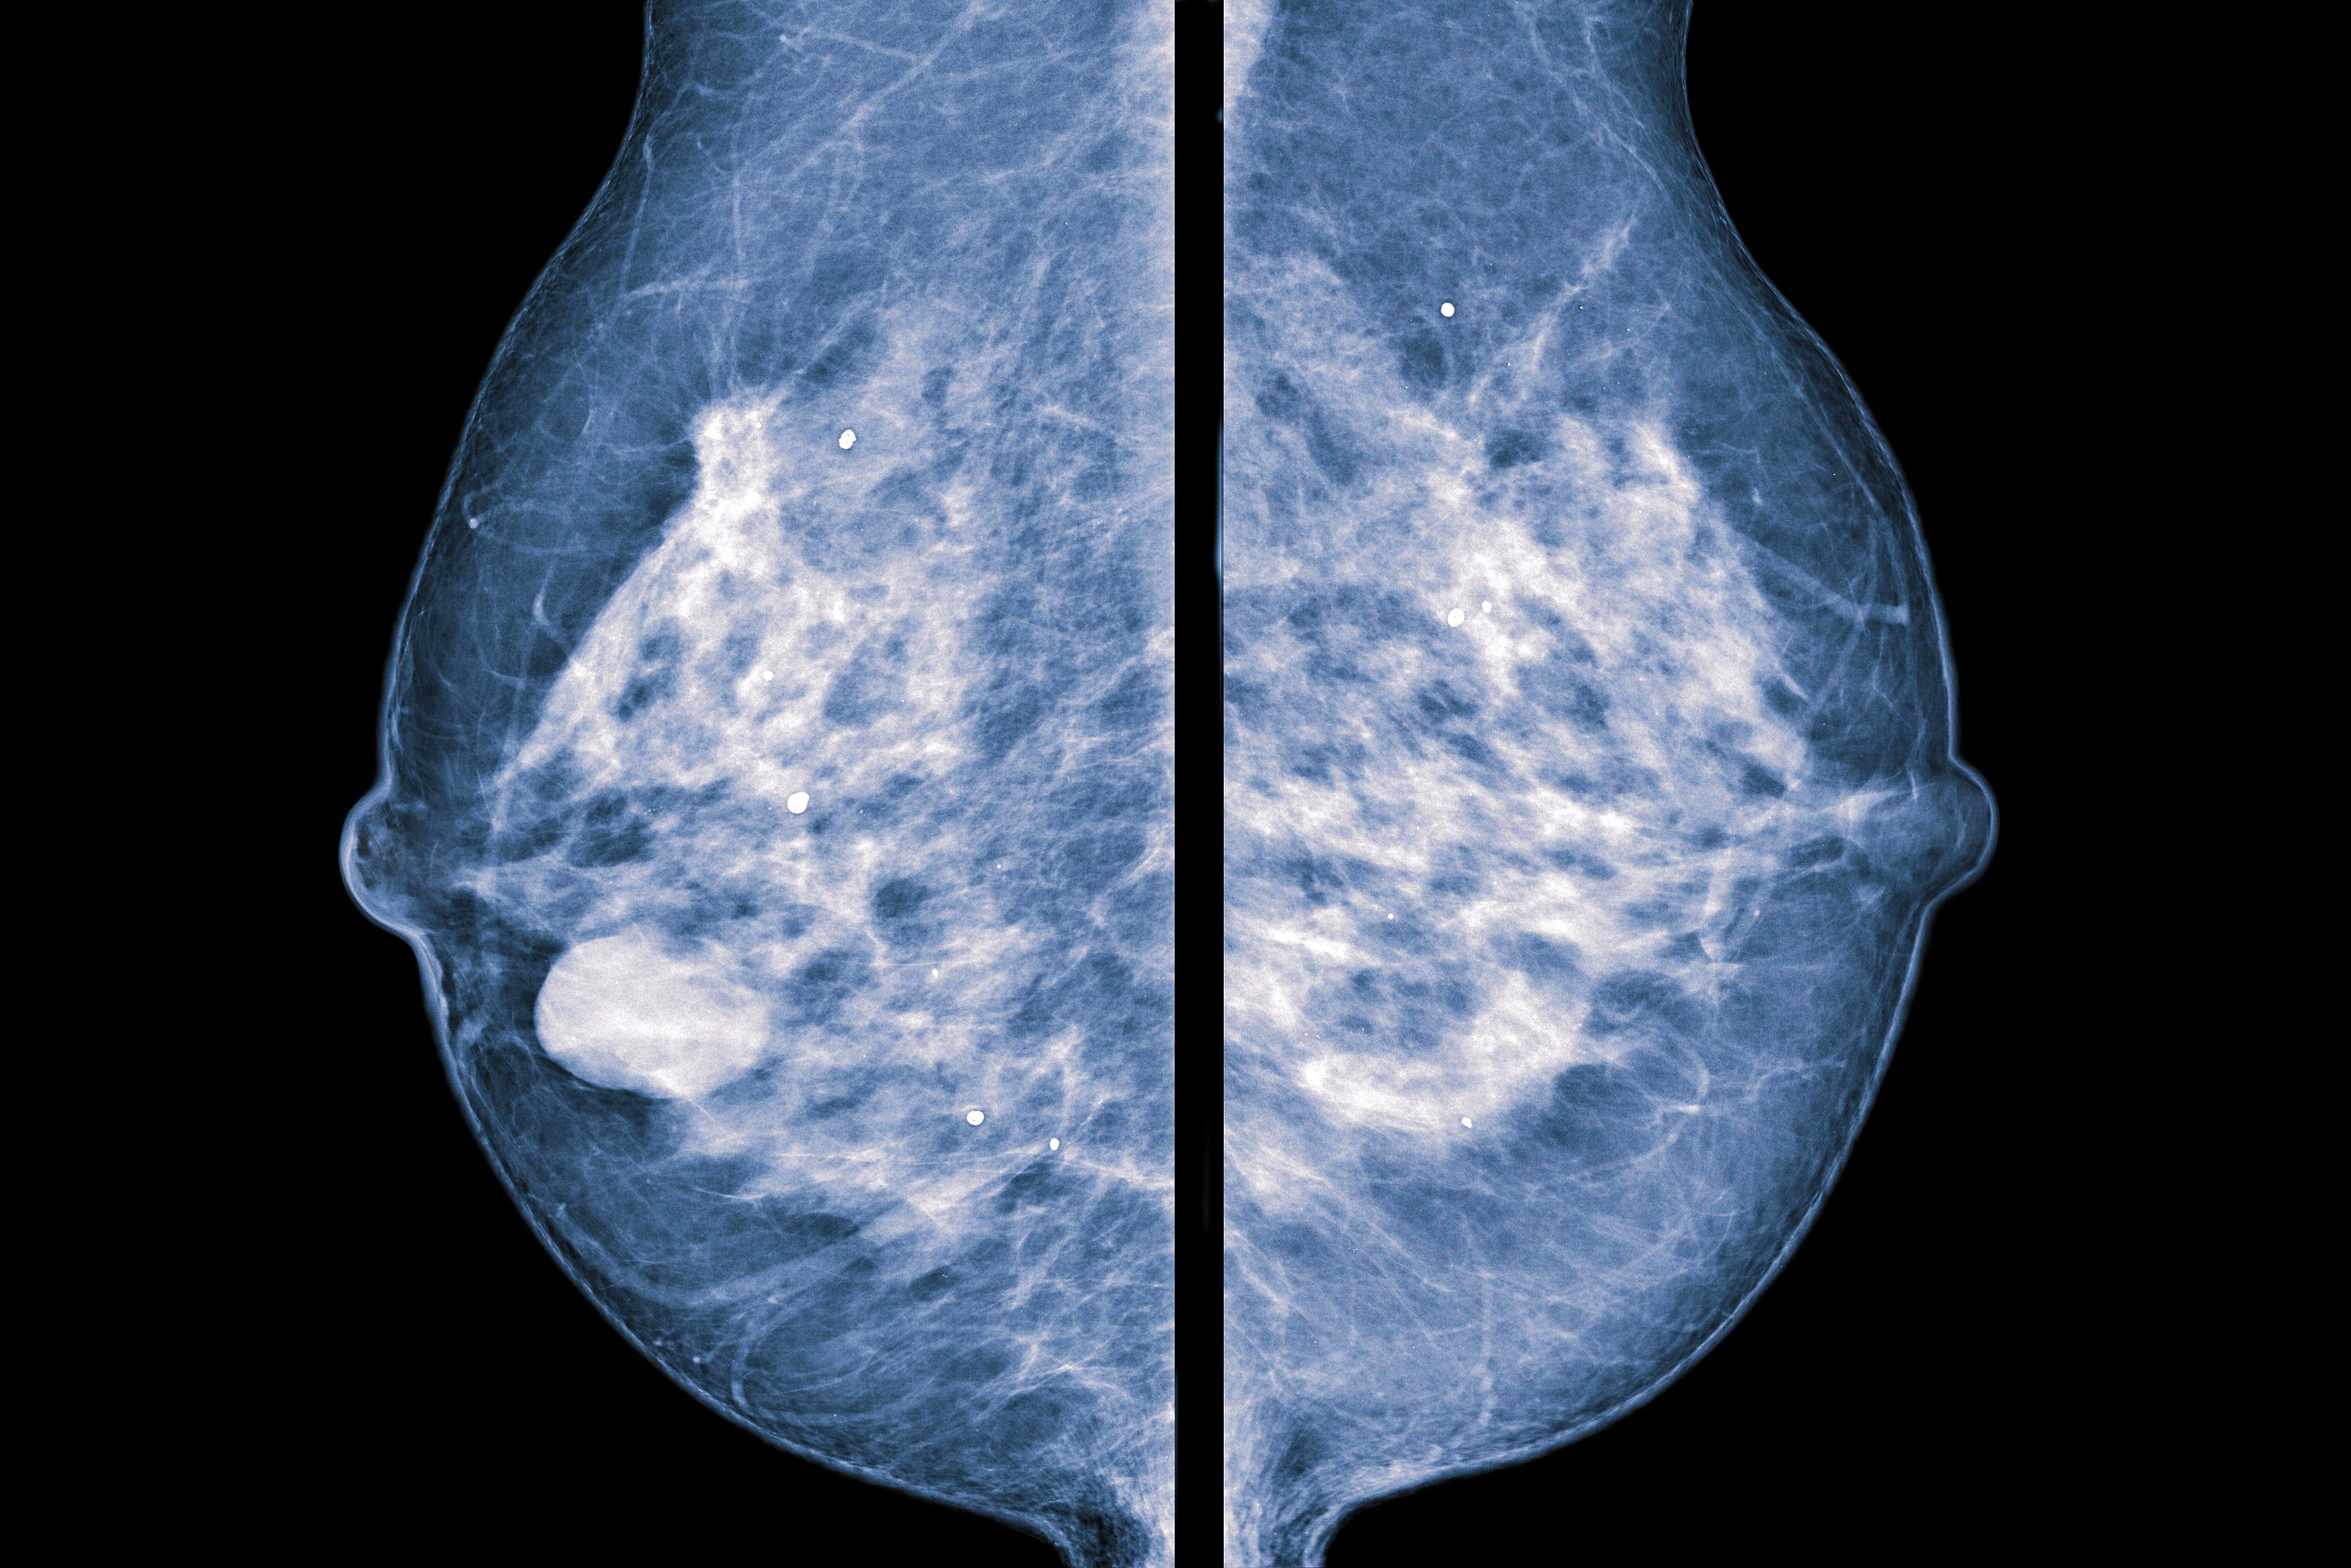

Mammogram

A mammogram is an X-ray of your breast. Mammograms can detect tumors that are too small to be felt by you or your health care provider. Detecting breast cancer as early as possible is very important. The earlier it is detected and treated, the better.

Your screening mammogram will be performed by a technologist called a mammographer who is specially trained in mammogram positioning and techniques. The mammographer uses a special, low dose X-ray machine to create an image of the breast tissue. The machine has specialized paddles used to compress the breast to help detect findings that may be too small to feel.

Compression of the breast is sometimes uncomfortable. However, it is very important as it ensures a clear view of the breast tissue and reduces the amount of radiation needed to create your exam images.

Each breast will be compressed for 10 to 20 seconds while you are given instructions on when to hold your breath. Your mammogram images will be sent to a radiologist who will carefully review them to see if there is any need for additional testing. Your health care provider will then receive the finalized report.

It is not uncommon for your first mammogram to show findings that may require additional testing since there are no previous mammograms that can be used for comparison. Most findings are not cancer and are resolved by the additional tests.

An additional mammogram to evaluate a potential trouble spot is called a diagnostic mammogram. It will focus specifically on the area in question. In some cases, a breast ultrasound also may be recommended to evaluate the area.